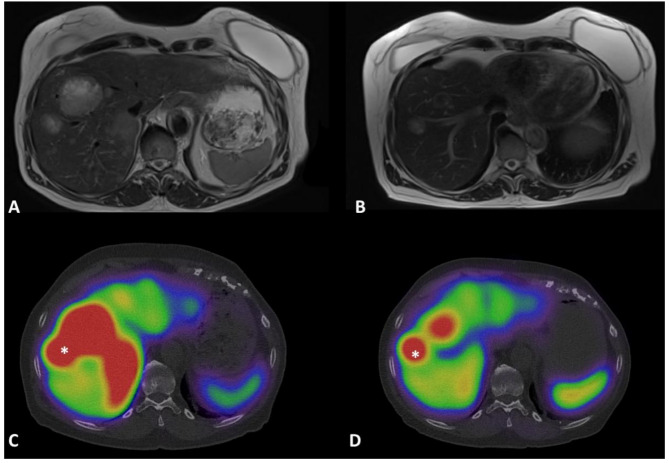

背景:177Lu-DOTATATE肽受体放射性核素治疗已成为晚期小肠神经内分泌肿瘤(siNET)患者的二线治疗方法。治疗效果在治疗结束几个月后根据RECIST标准进行评估。治疗后闪烁成像(PTS)可以在每个周期后进行,但其在早期反应评估中的价值存在争议,特别是在临床常规中缺乏量化的情况下。现在可以使用新的量化模块,实现自动SUV计算。本研究的主要目的是评估定量PTS在第一(C1)和第二(C2)周期之间的SUV演变在预测治疗反应中的价值。所有到我们中心接受177Lu-DOTATATE治疗的siNET患者均被纳入研究。在C1和C2的PTS SPECT/CT上测量摄取最大的病变的SUVmax。∆计算SUVmax。∆SUVmax与6个月RECIST百分比之间采用线性回归。肿瘤代谢量(MTV)与临床参数的相对变化也进行了研究。结果:连续纳入12例进展性转移性siNET患者。1例患者在6个月时出现部分缓解,另1例患者病情稳定。线性回归显示,6个月RECIST百分比和∆SUVmax与以下回归公式密切相关:6个月RECIST = -0.05 + 0.36 x∆SUVmax (p)结论:我们报道siNET患者的PTS∆SUVmax与6个月RECIST百分比之间存在显著联系。因此,定量成像可以早在C2期就预测177Lu-DOTATATE 6个月的疗效。这些结果需要在更大的人群中得到证实。

Background: peptide receptor radionuclide therapy with 177Lu-DOTATATE has become an established second-line treatment for patients with advanced small intestine neuroendocrine tumors (siNET). Treatment efficacy is assessed several months after the end of treatment and is based on RECIST criteria. Post-therapy scintigraphy (PTS) can be performed after each cycle, but its value in early response assessment is debated particularly given the lack of quantification available in clinical routine. New quantification modules are now available, enabling automatic SUV calculation. The main goal of this study is to assess the value of the evolution of SUV between the first (C1) and the second (C2) cycle on quantitative PTS in predicting response to treatment. All patients with siNET referred to our center for treatment with 177Lu-DOTATATE were included. The SUVmax of the lesion with the greatest uptake was measured on PTS SPECT/CT at C1 and C2. ∆SUVmax was calculated. Linear regression between ∆SUVmax and 6-month RECIST percentage was used. Relative changes in tumor metabolic volume (MTV) were also studied along with clinical parameters.

Results: twelve consecutive patients with progressive metastatic siNET were included. One patient showed partial response at 6 months, the other were considered as stable disease. Linear regression showed that 6-month RECIST percentage and ∆SUVmax were strongly correlated with the following regression formula: 6-month RECIST = -0.05 + 0.36 x ∆SUVmax (p < 0.001). ∆MTV was not predictive of response.

Conclusion: we report a significant link between PTS ∆SUVmax and 6-month RECIST percentage in patients with siNET. Quantitative imaging would thus enable the prediction of 6-month response of 177Lu-DOTATATE as early as C2. These results need to be confirmed on a larger population.